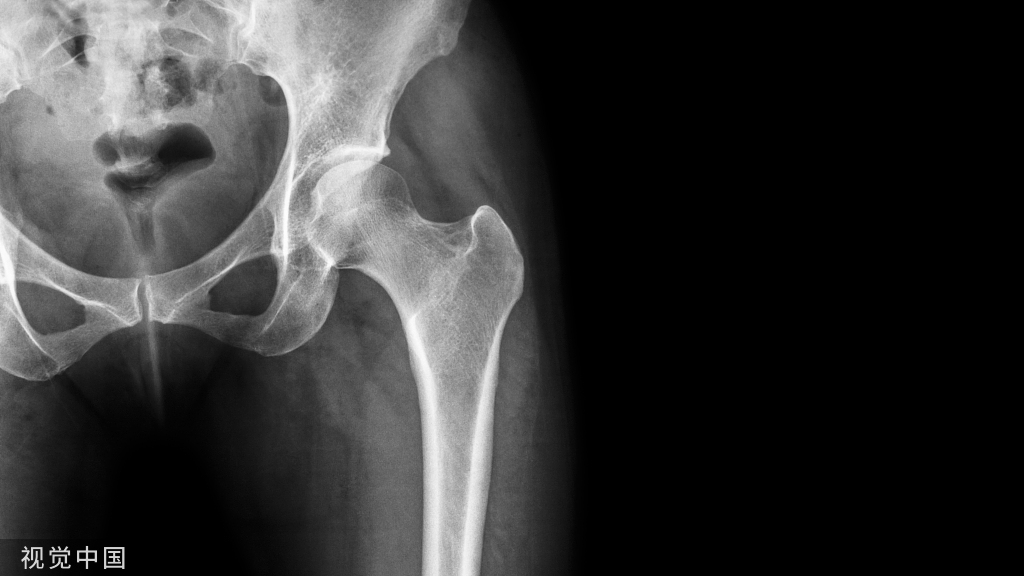

05股骨近端骨折

股骨颈骨折常发生在老年人,头下型骨折最常见,但是当股骨外旋或有明显的关节炎骨赘形成时,骨折较难发现。此外,肥胖和骨量减少增加髋部 X 片诊断难度,所以需格外注意。

因骨结构重叠影响,股骨转子骨折发生轻度移位时亦很难发现,加做一个不同角度的 X 线片有助于诊断(图 7)。